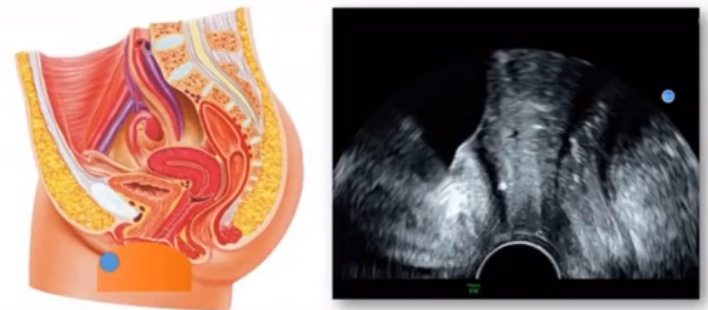

位于輸卵管的后下方,子宮兩側(cè)的后上方;借卵巢系膜與子宮闊韌帶后層相連。正常成人卵巢約4x3x2cm,跟睪丸的數(shù)值差不多,都是性器官,絕經(jīng)后卵巢萎縮變小、變硬。所以絕經(jīng)后婦女很難找到卵巢,主要功能:生殖和內(nèi)分泌功能分泌性激素。女性的第二性征。女性內(nèi)生殖器的血管分布,動(dòng)脈有子宮動(dòng)脈,卵巢動(dòng)脈,陰道動(dòng)脈,陰部內(nèi)動(dòng)脈。靜脈它是與動(dòng)脈伴行。重要了解的是子宮動(dòng)脈,子宮動(dòng)脈是髂內(nèi)動(dòng)脈前干的重要分支,妊娠時(shí)候血流速度會(huì)增加的,為無創(chuàng)性檢查胎盤血管阻力的方法。未孕期頻譜為高阻力低舒張波形;正常妊娠時(shí)血流速度增加,血流阻力下降。